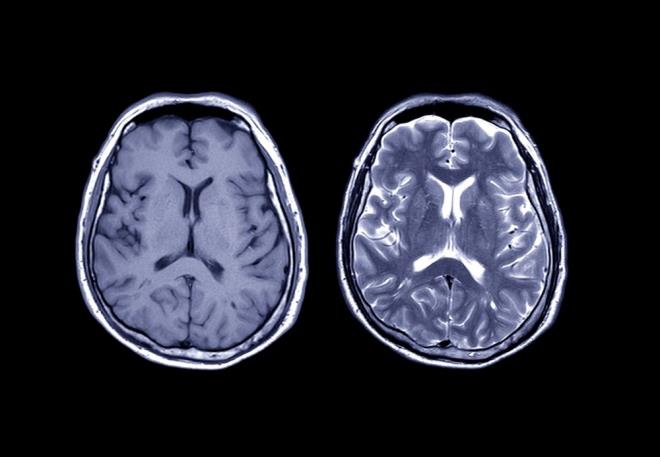

5. Louth, sözlerine şu şekilde devam etti:    "İnsan ve fare beyni aynı temel işlevlere sahip. Ancak, insan beyninde çok daha fazla karmaşık yapı var. Hücre tiplerinde ve belirli reseptörlerde büyük farklılar var. Bu nedenle doğrudan insan dokusunda test yapabilmek eşsiz bir fırsat.?

Louth, sözlerine şu şekilde devam etti: "İnsan ve fare beyni aynı temel işlevlere sahip. Ancak, insan beyninde çok daha fazla karmaşık yapı var. Hücre tiplerinde ve belirli reseptörlerde büyük farklılar var. Bu nedenle doğrudan insan dokusunda test yapabilmek eşsiz bir fırsat.?